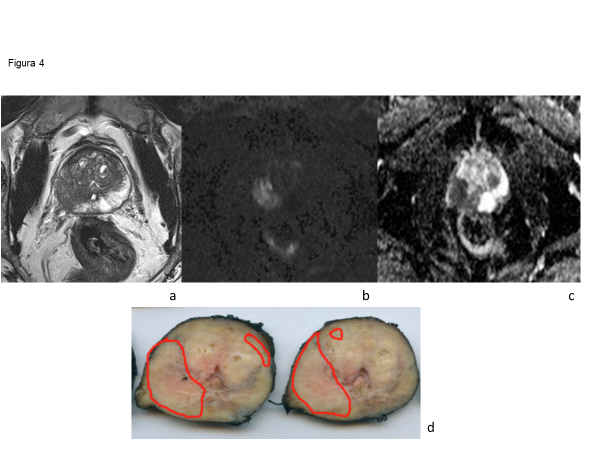

PI-RADS v2 (2015) y su posterior actualización PI-RADS v2.1 (2019) no apunta a detectar todos los tumores prostáticos, ya que presenta baja sensibilidad para la detección de enfermedad de bajo volumen (<0.5 ml) y CP de bajo riesgo (GS 3+3). Esto permite que la estrategia de RMmp-biopsia dirigida diminuya los sobrediagnósticos y sobretratamientos, como también reduce el número de pacientes sometidos a biopsia que se encuentran en vigilancia activa. Lesiones de alto grado y volumen se detectan con mayor facilidad y presentan categorías de PI-RADS más alto (PI-RADS score 4 y 5) (Figura 4).